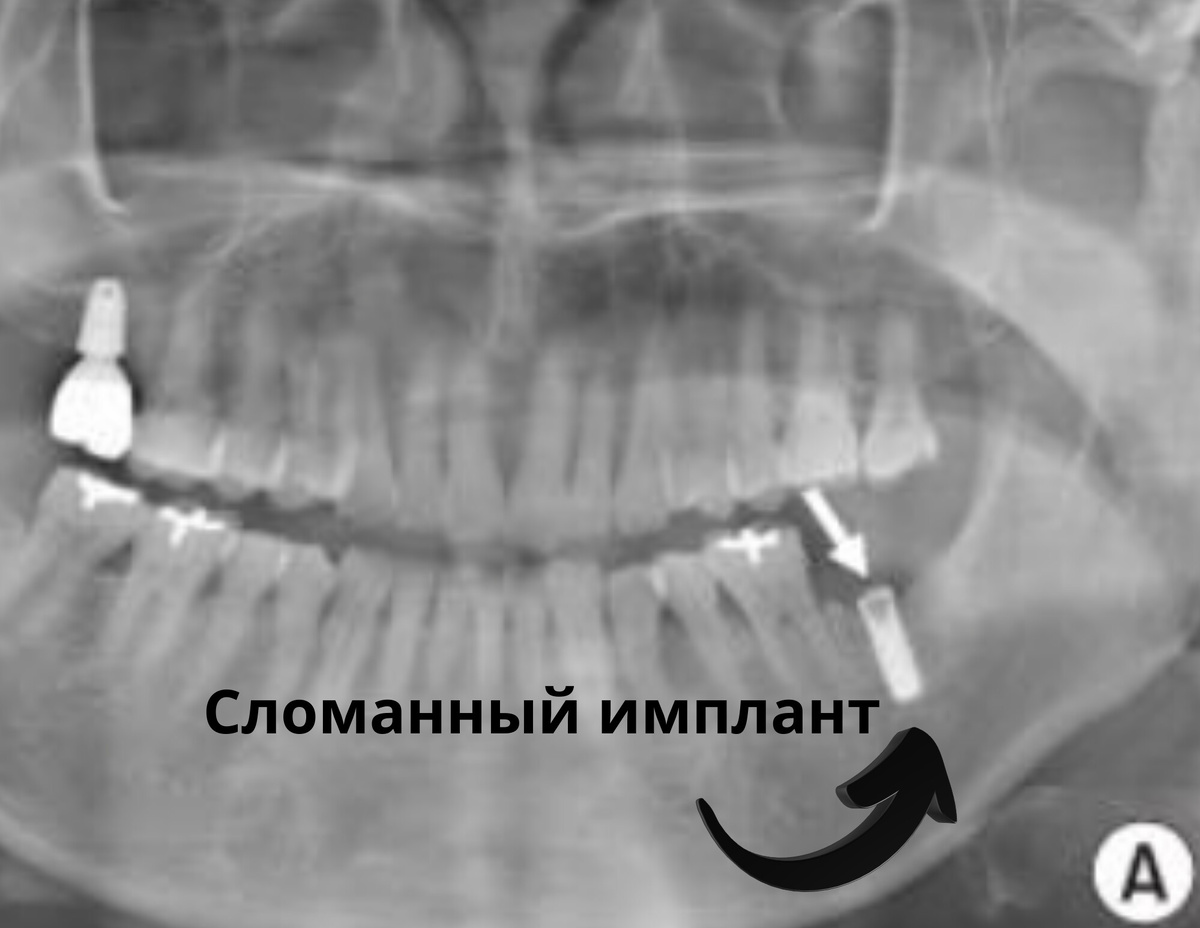

Критические поломки конструкции (5-6%). Коронка или абатмент ломаются от нагрузки, материал крошится, разрушается внутренняя резьба. Это приводит к замене поврежденной части (часто без удаления импланта), ведет к потере функциональности импланта или требуют хирургического вмешательства. Это дешевле, чем полная потеря.